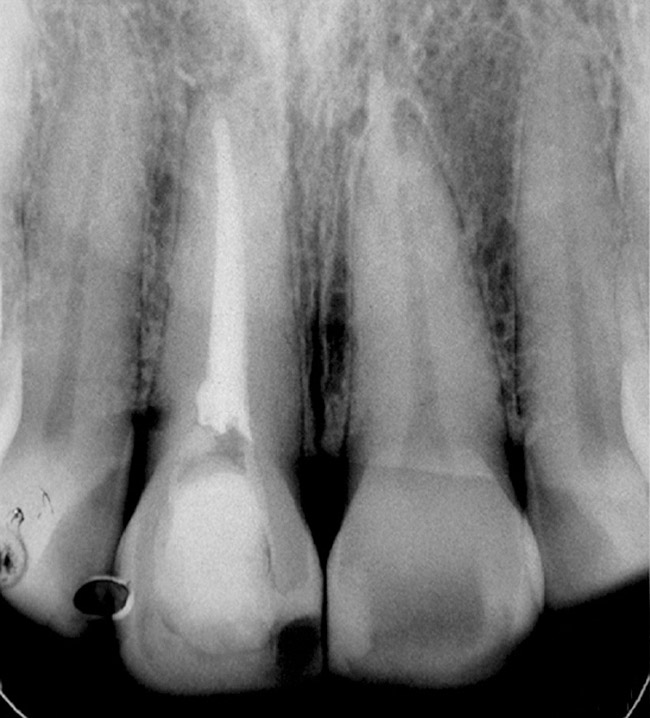

Figure 1a  Panoramic (A) and periapical radiographs (B, C) reveal the absence of periapical rarefaction in the area of the upper right central incisor. However, evidence of apical periodontitis can be seen clearly using the CBCT21 (D, E).

Figure 1a

Figure 1b  Panoramic (A) and periapical radiographs (B, C) reveal the absence of periapical rarefaction in the area of the upper right central incisor. However, evidence of apical periodontitis can be seen clearly using the CBCT21 (D, E).

Figure 1b

In addition to linear accuracy, it has been suggested that CBCT can have diagnostic accuracy with regards to periapical lesions.17-19 In one of these studies,17 periapical lesions were analyzed with CBCT, then surgically excised and biopsied to compare with histology. The authors found comparable results. Although the study showed promising results with CBCT, the researchers conceded that histology remains the gold standard in the diagnostic armamentarium. In another study,19 the ability to identify periapical lesions was assessed using radiographs and spiral CT. With CT, 100% of lesions were identified, while only 78% were identified with radiographs alone. Concomitantly, the location of the lesions proximal to the inferior alveolar nerve was visualized more readily with CT (100% vs 39%). Figure 1A through Figure 1E illustrate a case in which an endodontically treated tooth appeared normal on panoramic and periapical radiographs. Only CBCT showed the presence of apical pathology.6